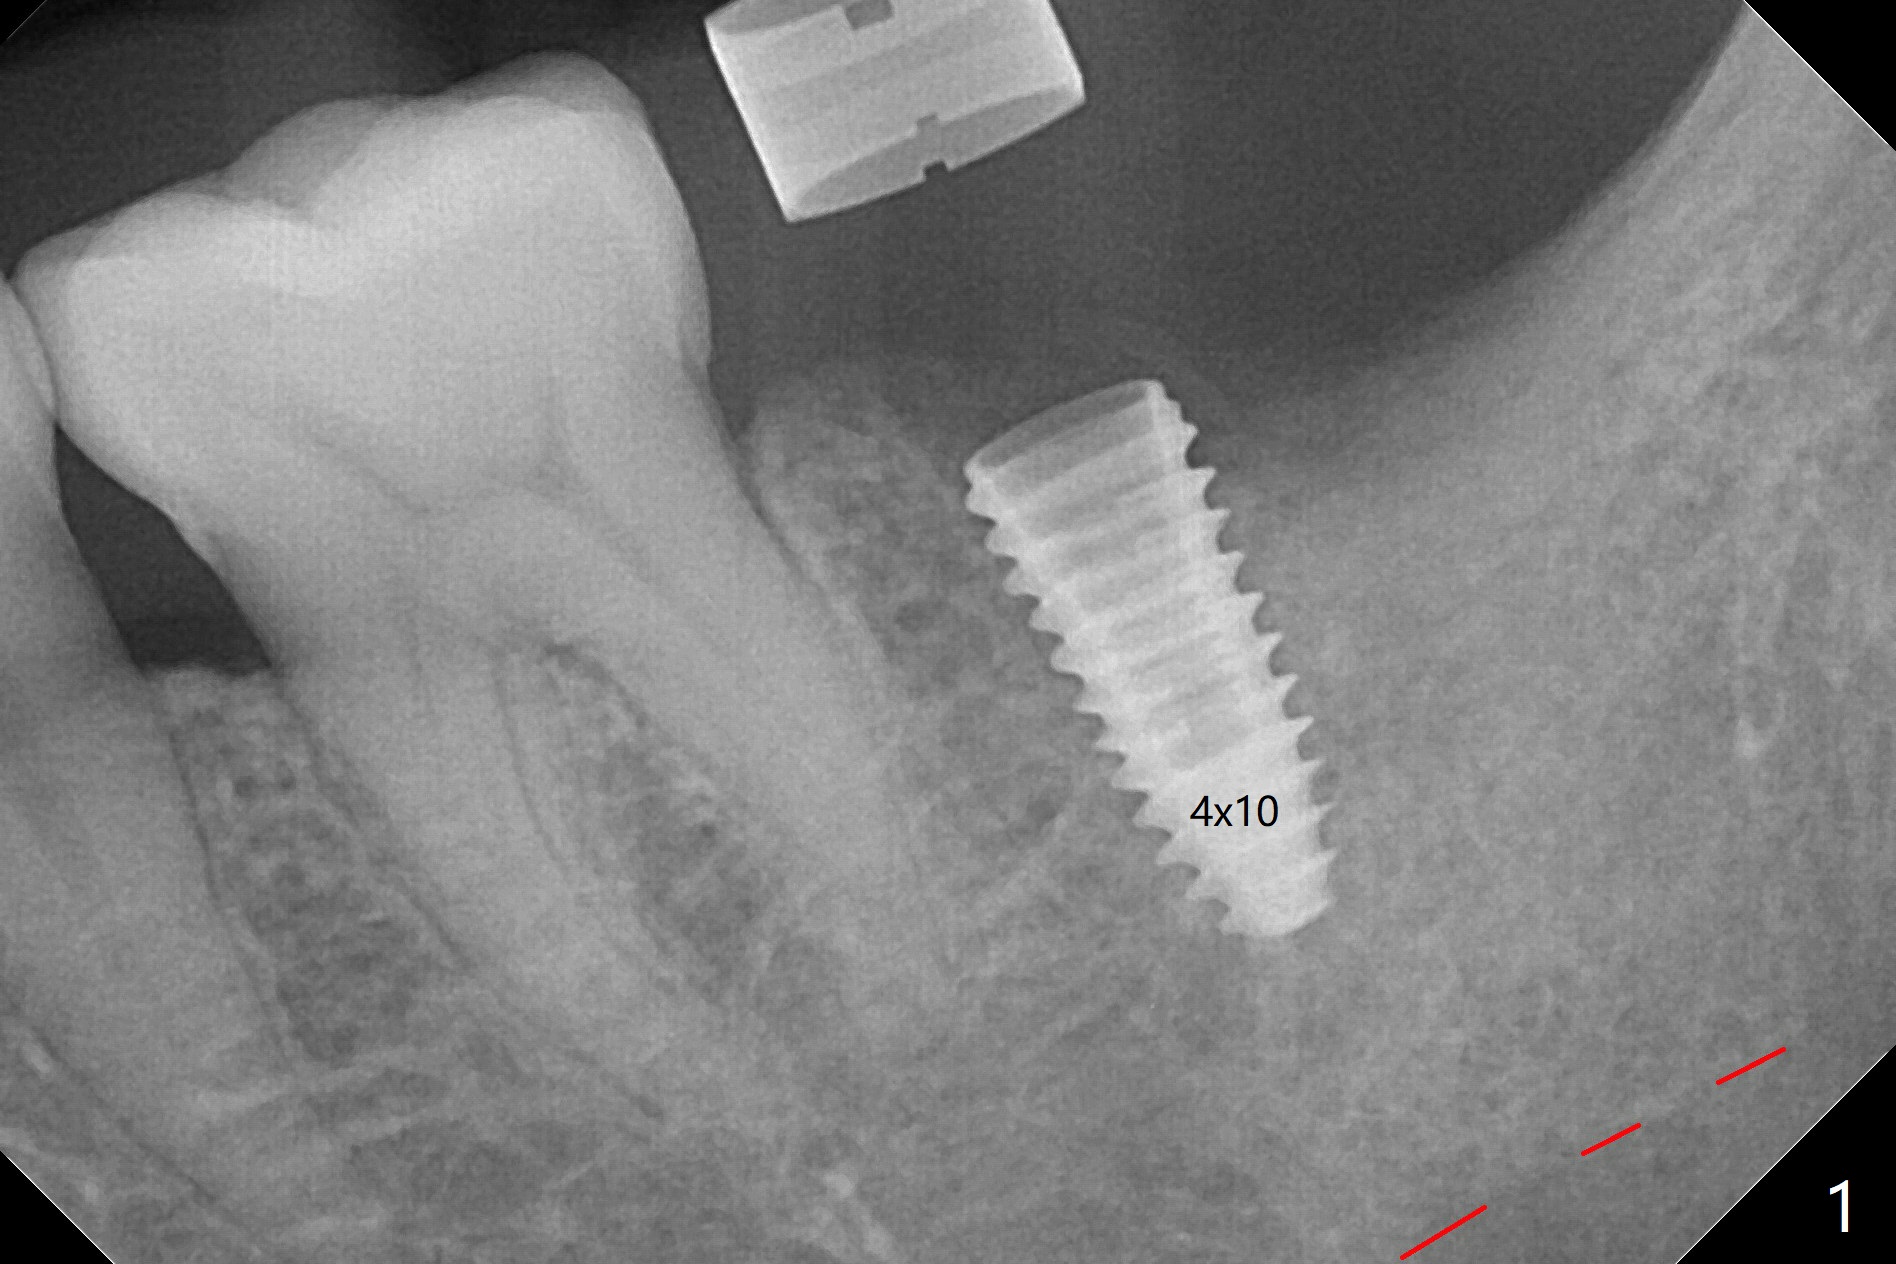

左下7钻洞中出现三种情况:容易出血(血小板减低(9万)),疼痛(根尖肉芽肿)和骨质疏松,钻洞深度还没达到,使用短小报废植体拍摄根尖片(图一),之后下颌牙槽神经阻断,钻洞没有疼痛,但是未注意骨质疏松问题,按照正常钻洞顺序,所以正式植体扭力低,10 Ncm(图二),放置骨粉和不可吸收膜,PTFE缝合(图三)。术后一周膜舌侧稍微外翻(剪太小些,图四)。病人将术后五周回来去除膜,之后拍摄咬翼片证实骨粉丧失与否。其实病人提前回来,抱怨缝线不适,膜不翼而飞(图五,折线后),患侧咀嚼,因为对侧下颌第二磨牙疼痛又不肯拔除。The bone graft placed at the time of immediate implant (Fig.3 *) is apparently changing into the normal bone 4 months postop before uncover (Fig.6). After removal of the bone coronal to the implant with a curette, a 4x4(3) mm pair abutment is placed (Fig.7). Two weeks later the abutment screw is torqued at 20 Ncm.